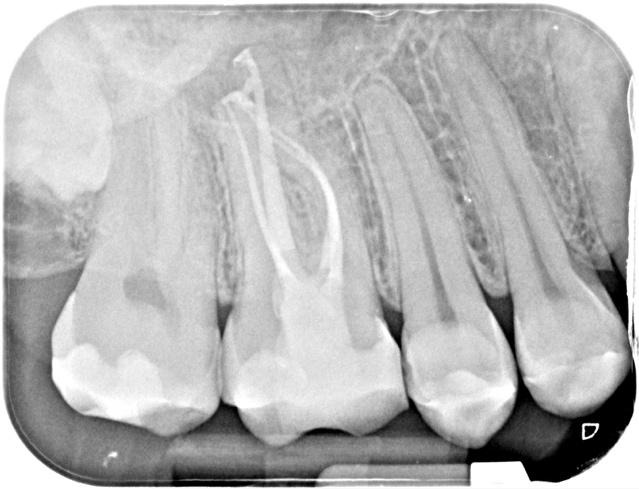

File System

VDW Rotate 1504, 2005 and 2504 was selected for this tooth to try and preserve as much pericervical (PCD) dentine as possible given the patient’s younger years. Dentsply’s Wave One Gold Large (WOGL) was used for the wider palatal canal.